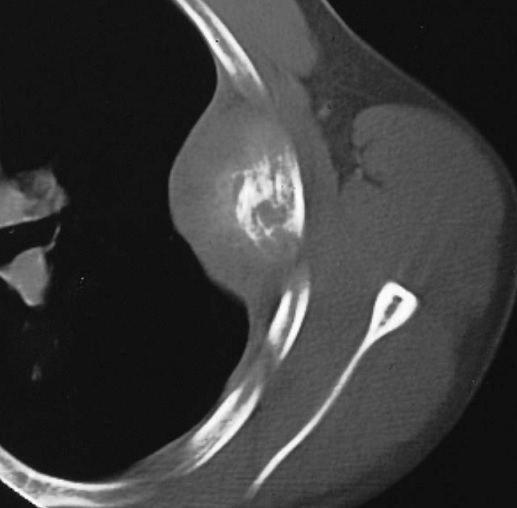

Image radiologique TDM d'une

tumeur metastatique secondaire de type condensant (

fleche rouge ) de l'arch posterieure du côte

thoracique gauche |